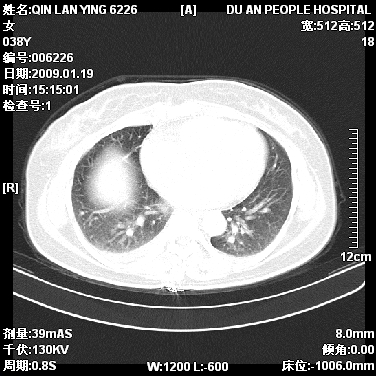

女,38岁,胸疼1个月。wbc:1万4

考虑----右肺中心型肺癌---阻塞性肺炎-----纵膈淋巴结及胸膜转移----肝脏转移

1)右肺中央型肺癌并右肺上叶阻塞性肺炎、节段性肺不张,纵隔淋巴结转移、右侧胸膜转移、肝脏转移。2)右侧胸腔少量积液。

1、右侧中央型肺癌并阻塞性肺不张,纵隔内、主动脉弓旁、右肺门淋巴结及肝脏转移可能性大,建议纤支镜进一步检查。

2、右侧胸腔积液。

本病例有几个容易诊断的地方:1、右肺上叶前段支气管闭塞,肺不张。2、淋巴结明显肿大。3、肝脏多个类圆形低密度影呈“牛眼征”改变,高度提示转移。

从影像学角度分析      右肺上叶中央型肺癌,并阻塞性不张、肺炎,纵隔淋巴结、膈顶淋巴结转移。

肝内两个大小不等低密度结节,内可见更低密度影,首先考虑肝内转移瘤,但联想到患者wbc1万4,建议楼主还是做个增强比较明确,除外肝脓肿的可能。